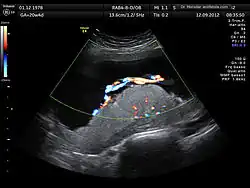

A 3D Power Doppler image of vasculature in 20-week placenta -